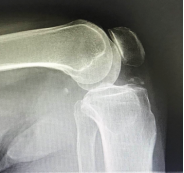

反肩关节置换术

半肩置换术